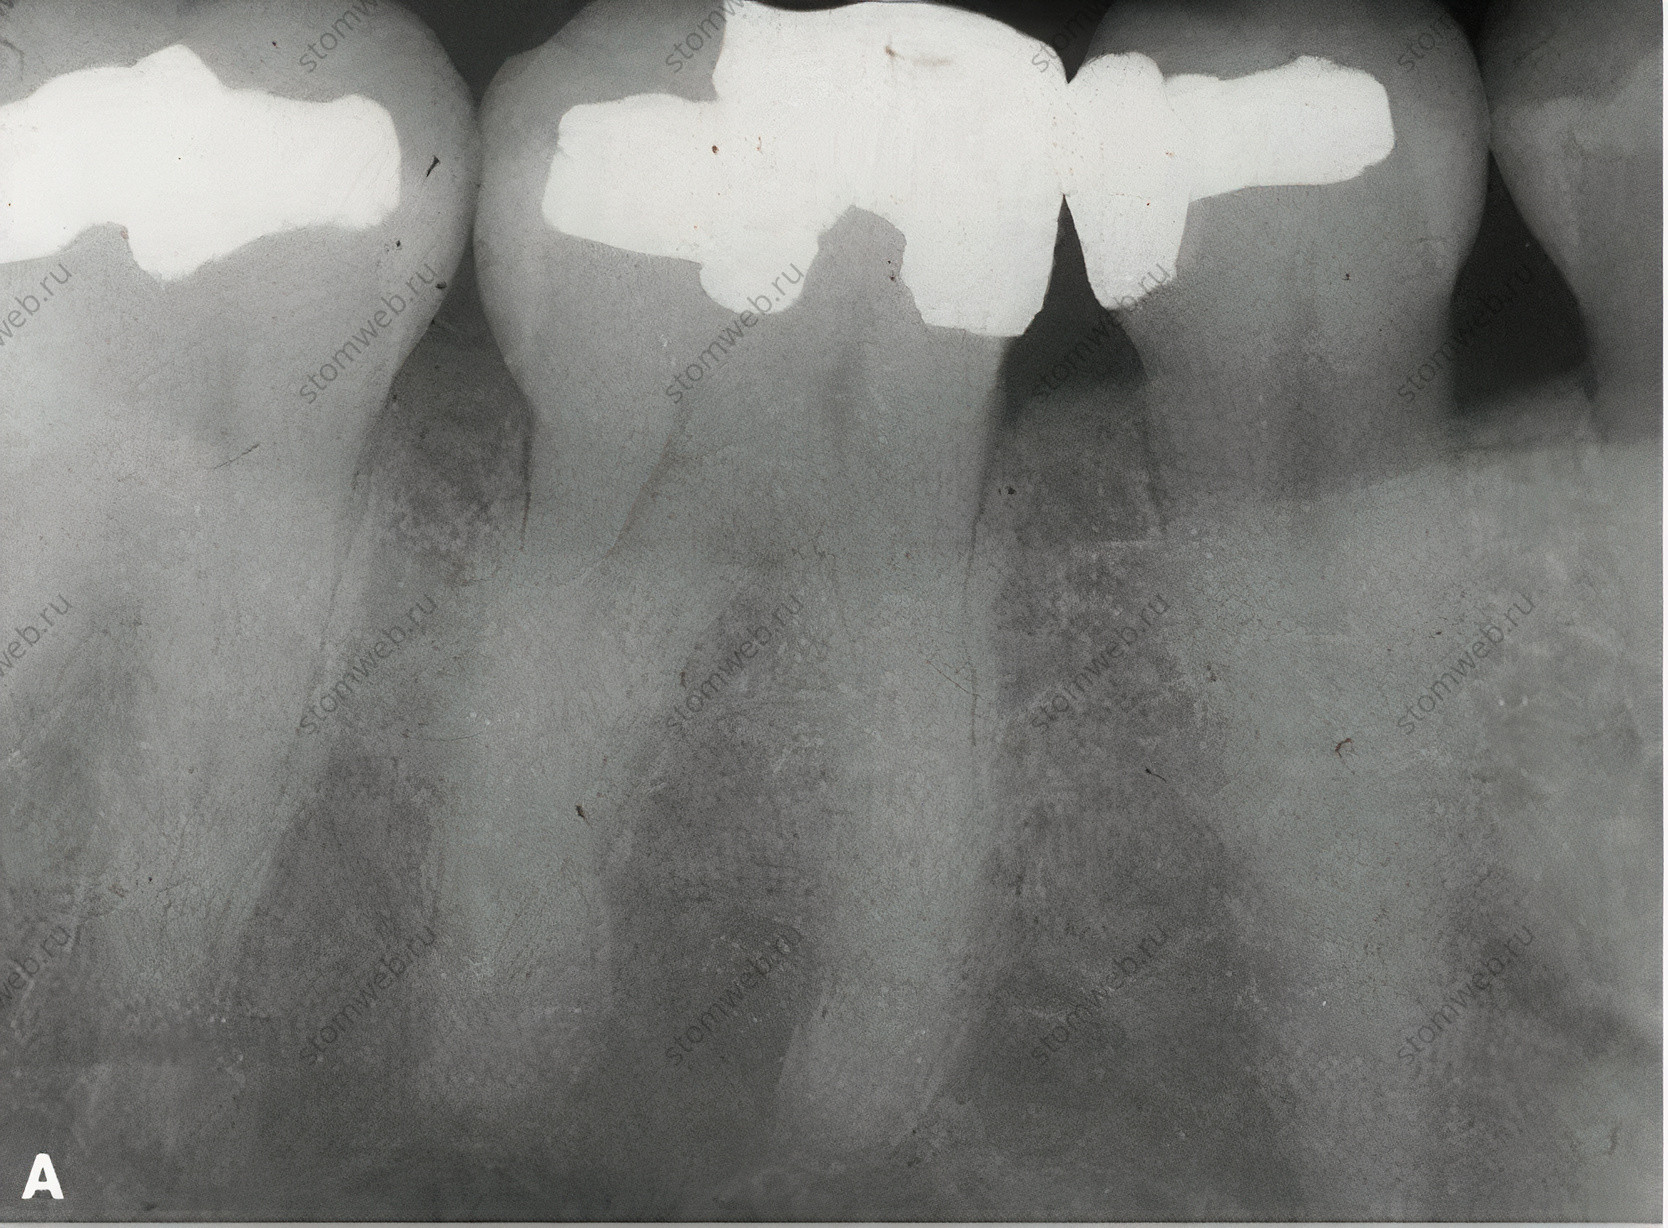

Рисунок 19 Диагностическое бандажирование зуба с трещиной коронки. A. Рентгенограмма первого моляра нижней челюсти с симптоматической трещиной коронки на дистальной стороне зуба. Поскольку линия перелома находится в мезио-дистальной ориентации, на снимке она не видна. Б. При диагностике (на основании симптомов и клинических данных) обратимого пульпита на зуб цементируют кольцо. C. Фотография сделана через 2 недели, когда пациент сообщает о полном отсутствии симптомов. Теперь пациенту может быть предложен вариант коронки с полным покрытием с информированием о том, что около 20% таких зубов могут потребовать эндодонтического лечения позже; некоторые пациенты могут предпочесть профилактическое лечение корневых каналов перед установкой коронки.